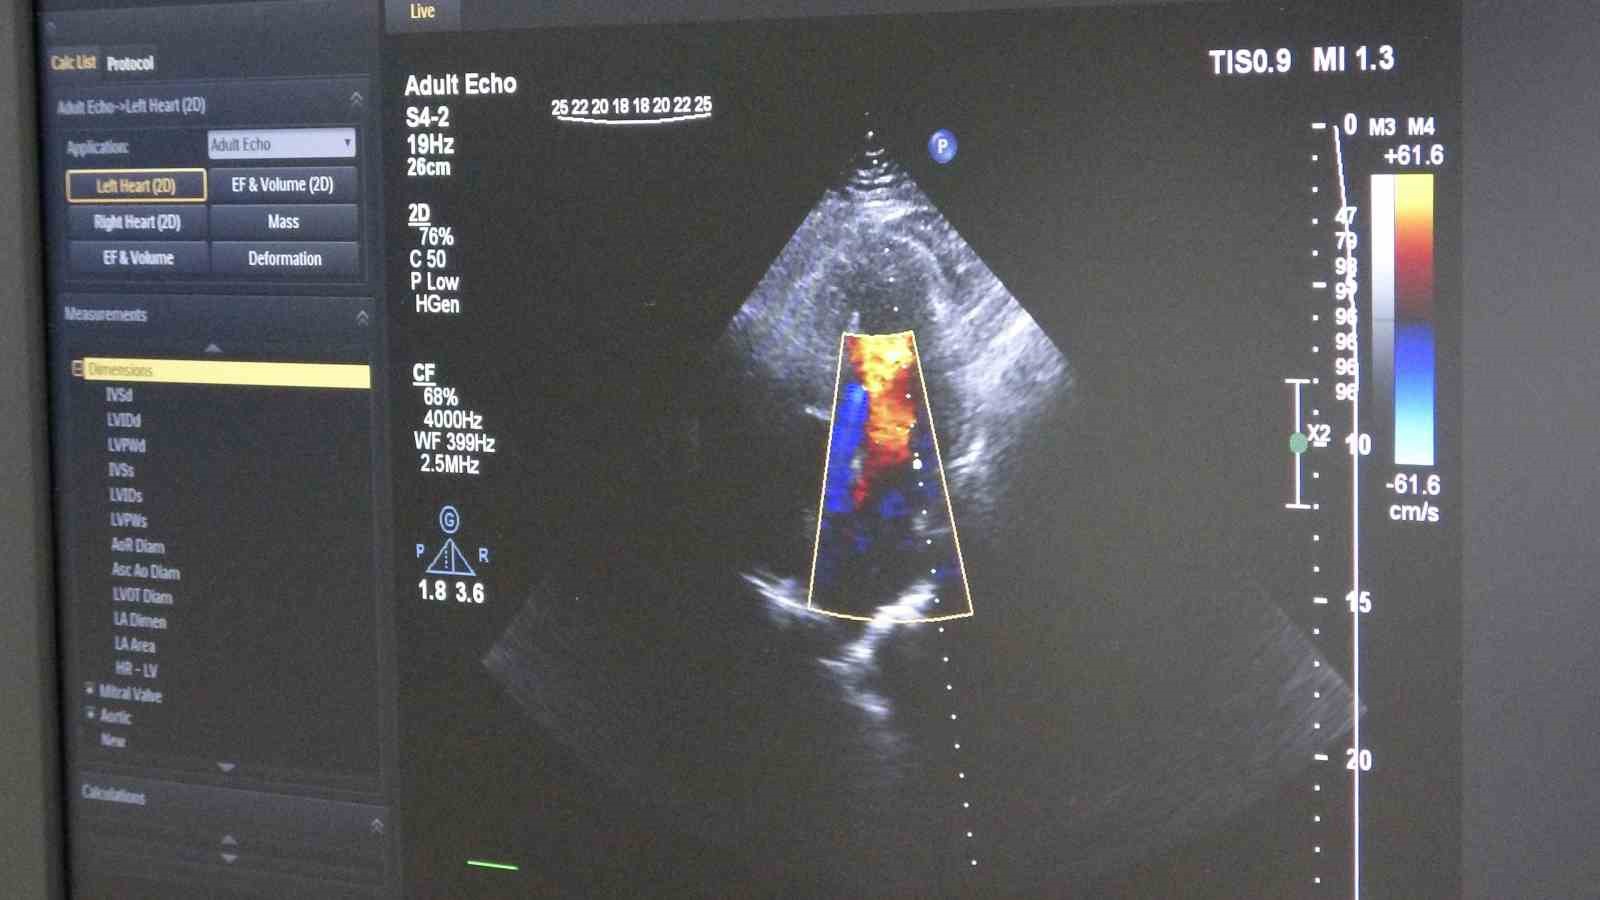

Gelişen teknolojiyle birlikte öne çıkan tedavi yöntemlerinden biri olan ilaç kaplı balon uygulaması, damara kalıcı metal yapı bırakmadan tedavi imkânı sunuyor. Bu yöntemde, özel ilaç kaplı balon damar içerisinde genişletilerek hem darlık gideriliyor hem de ilaç doğrudan damar duvarına etki ediyor.

Ordu Eğitim ve Araştırma Hastanesi Kardiyoloji Kliniği’ne göğüs ağrısı şikâyetiyle başvuran 55 yaşındaki erkek hastada yapılan anjiyografide, 3 damarda ileri derecede darlık tespit edildi. İlk değerlendirmede hastaya bypass ameliyatı önerildi. Ancak hastanın ameliyatı kabul etmemesi üzerine alternatif tedavi seçenekleri değerlendirildi. Yapılan detaylı incelemeler sonucunda hasta için ilaç kaplı balon yöntemiyle girişimsel tedavi planlandı. Uygulanan işlemle hastanın 3 damarındaki tıkanıklıklar stent kullanılmadan açılırken, hasta ise tedavinin 2’nci günü taburcu edildi.

Tedavi sürecinde damar yapısının ayrıntılı incelendiğini belirten Dereli, "İşlem öncesinde intravasküler ultrason (IVUS) ile damar duvarını değerlendiriyoruz. Ayrıca fraksiyonel akım rezervi (FFR) ile darlığın kan akımına etkisini ölçüyoruz. Bu yöntemler, doğru karar vermemizi ve başarılı sonuç elde etmemizi sağlıyor" diye konuştu.